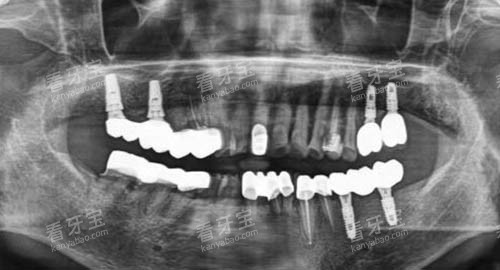

种植牙可是现在修复缺失牙齿的热门方式,好多人牙齿掉了都想着种一颗。仁寿丽齿传世口腔在这方面提供了多种选择,价格也各有不同。

国产种植牙:2500 元起

韩国登腾种植牙:3980 元起

韩国纽百特种植牙:3980 元起

美国皓圣种植牙:5980 元起

瑞典诺贝尔种植牙:7980 元起

瑞士 ITI 亲水种植:11800 元起

全口半固定种植:20000 元起

即刻负重种植:7680 元起